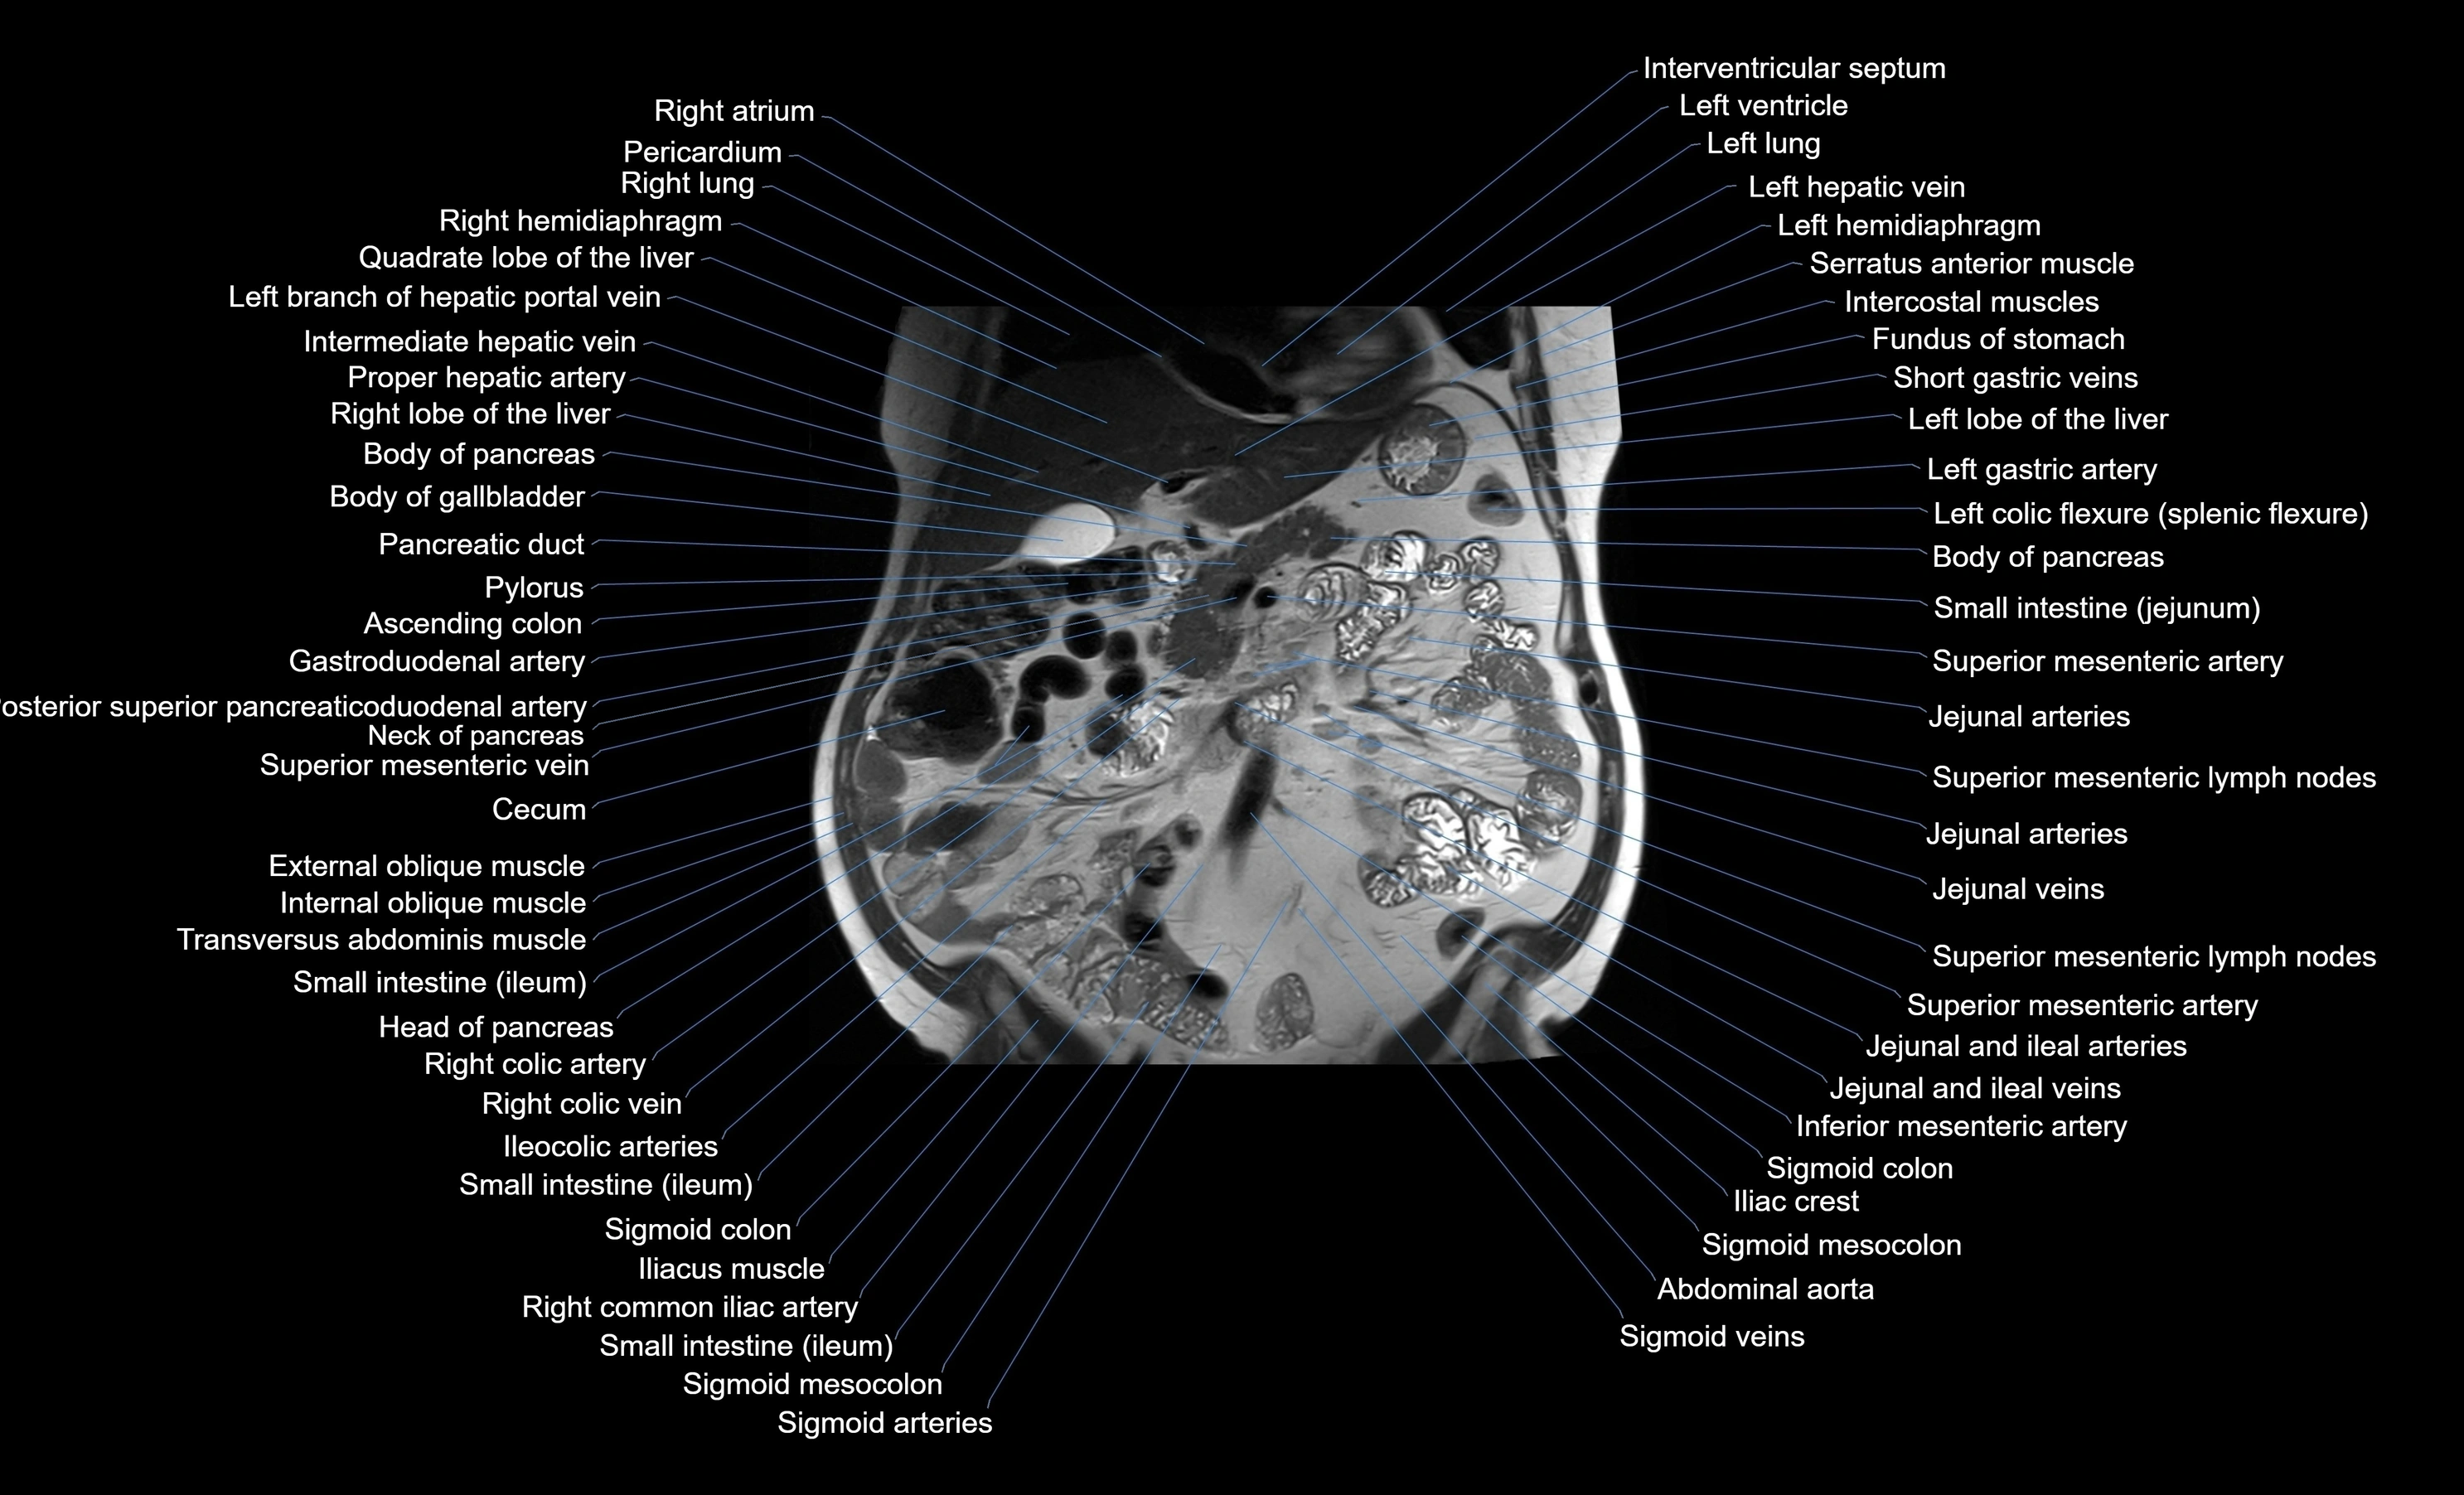

MRI images